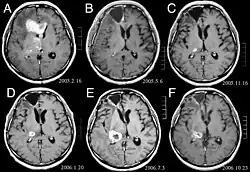

Primair lymfoom van het centrale zenuwstelsel is goed voor ongeveer 2 procent naar 3 procent van alle hersentumoren bij patiënten met een normaal immuunsysteem. Ze komen vaker voor bij mannen boven de 55 tot 60 jaar op. Bijna de helft van alle lymfomen komt voor bij patiënten ouder dan 60 jaar en ongeveer een kwart bij patiënten ouder dan 70 jaar jaar op. De incidentie lijkt toe te nemen met de leeftijd, maar de reden is nog steeds onduidelijk. Patiënten met een verzwakt immuunsysteem lopen een groter risico op het ontwikkelen van CZS-lymfoom, dus degenen die een orgaantransplantatie hebben ondergaan, hebben een aangeboren immunodeficiëntie of auto-immuunziekte, of zijn geïnfecteerd met het humaan immunodeficiëntievirus. HIV-geassocieerde hersenlymfomen zijn geassocieerd met het Epstein-Barr-virus, vooral bij patiënten met CD4-lymfocytentellingen van minder dan 500 cellen per kubieke millimeter in het bloed. De meeste CZS-lymfomen zijn grote B-cellymfomen van het type.

Patiënten lijden aan een verscheidenheid aan karakteristieke symptomen van een focale of multifocale massieve laesie. MRI toont meestal tumoren met homogene contrastversterking in de diepe periventriculaire witte stof. Multifocaliteit en inhomogene versterking zijn typisch voor patiënten met een verzwakt immuunsysteem. Analyse van CZS-lymfoom is uiterst belangrijk bij de differentiële diagnose van hersenneoplasie. Opgemerkt moet worden dat de toediening van corticosteroïden kan leiden tot het volledig verdwijnen van de versterking, waardoor de diagnose van de laesies moeilijk wordt. Als daarom CZS-lymfoom moet worden overwogen bij de differentiële diagnose, moeten corticosteroïden worden vermeden, tenzij het massa-effect een ernstig en onmiddellijk probleem bij de patiënt veroorzaakt.

In het verleden werd bestralingstherapie gegeven aan de hele hersenen (panencefalisch). De mediane overleving is ongeveer 12, zelfs met gelokaliseerde laesies Maanden. Herhaling treft meestal de plaats van de vorige verwonding en andere regio's. De reacties op chemotherapie zijn veelbelovender. Klinische onderzoeken waarin alleen methotrexaat in hoge doses werd gebruikt als de eerste behandeling en radiotherapie werd uitgesteld tot het moment van terugval of progressie, lieten een betere algehele overleving zien dan alleen radiotherapie. Nog effectiever was de combinatie van methotrexaat, vincristine, procarbazine, intrathecaal methotrexaat, cytarabine en panencefale radiotherapie en cytarabine, of het gebruik van intra-arteriële chemotherapie met intra-arterieel methotrexaat, intraveneus geïnjecteerd cyclofosfamide en etoposide na wijziging van de bloed- hersenbarrière met mannitol. De mediane overleving bij methotrexaattherapie was 24 tot 40 maanden veel hoger dan bij radiotherapie alleen (bereik 24 tot 40 maanden). In sommige gevallen wordt bestralingstherapie alleen gebruikt voor recidieven wanneer er een initiële regressie is met chemotherapie. Er zijn ook gevallen van lange overleving gemeld zonder radiotherapie.

Panencefalische bestralingstherapie gaat gepaard met een hoog risico op het ontwikkelen van dementie of leuko -encefalopathie. Dit risico kan worden verminderd door het ontwikkelen van effectieve tumorcontrolestrategieën die panencefale radiotherapie vermijden. De initiële therapie voor patiënten met een gecompromitteerd immuunsysteem is het verminderen van de oorzaken van immunosuppressie. De prognose voor deze patiënten is meestal slechter dan die voor patiënten met een normaal immuunsysteem. Als gevolg van begeleidende tumorinfecties en een over het algemeen suboptimale lichamelijke conditie kan chemotherapie bij deze immuungecompromitteerde patiënten vaak niet worden uitgevoerd. Net als bij andere hersentumoren hangt de respons op behandelingen af van leeftijd en lichamelijke conditie.